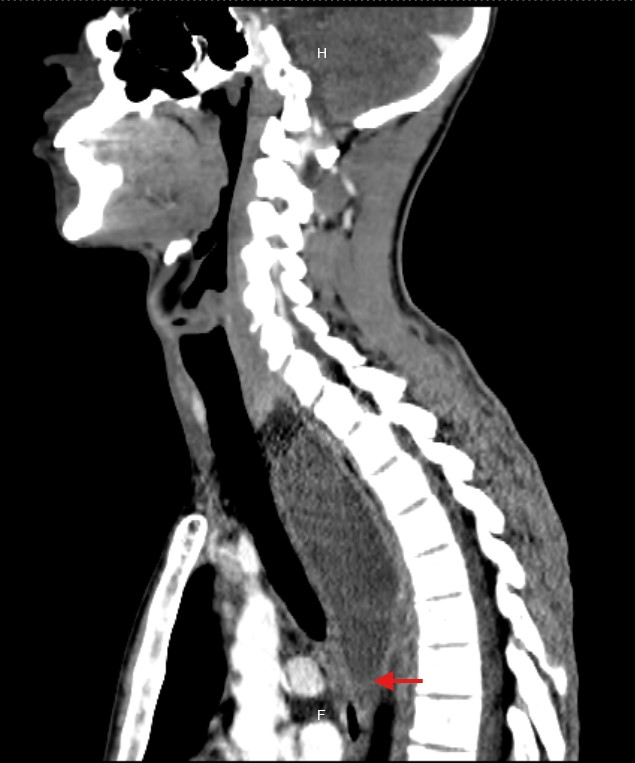

Due to the unclear etiology of the symptoms, combined with unremarkable initial studies and the subsequent development of dyspnea, a CT scan of the neck and thorax was performed. This revealed a large collection centered in the mediastinum, dissecting tissue planes and extending below the carina, reaching into the neck up to the left thyroid lobe. Gas was observed both within the collection and around the thyroid gland and mediastinum, with the esophagus displaced to the right by the mass effect of the abscess (Figure 1-5).

Figure 1 CT: Sagittal view showing an abscess extending from the left thyroid space to the superior mediastinum.

Figure 2 CT: Sagittal view showing mediastinal abscess extension up to the bronchial bifurcation.